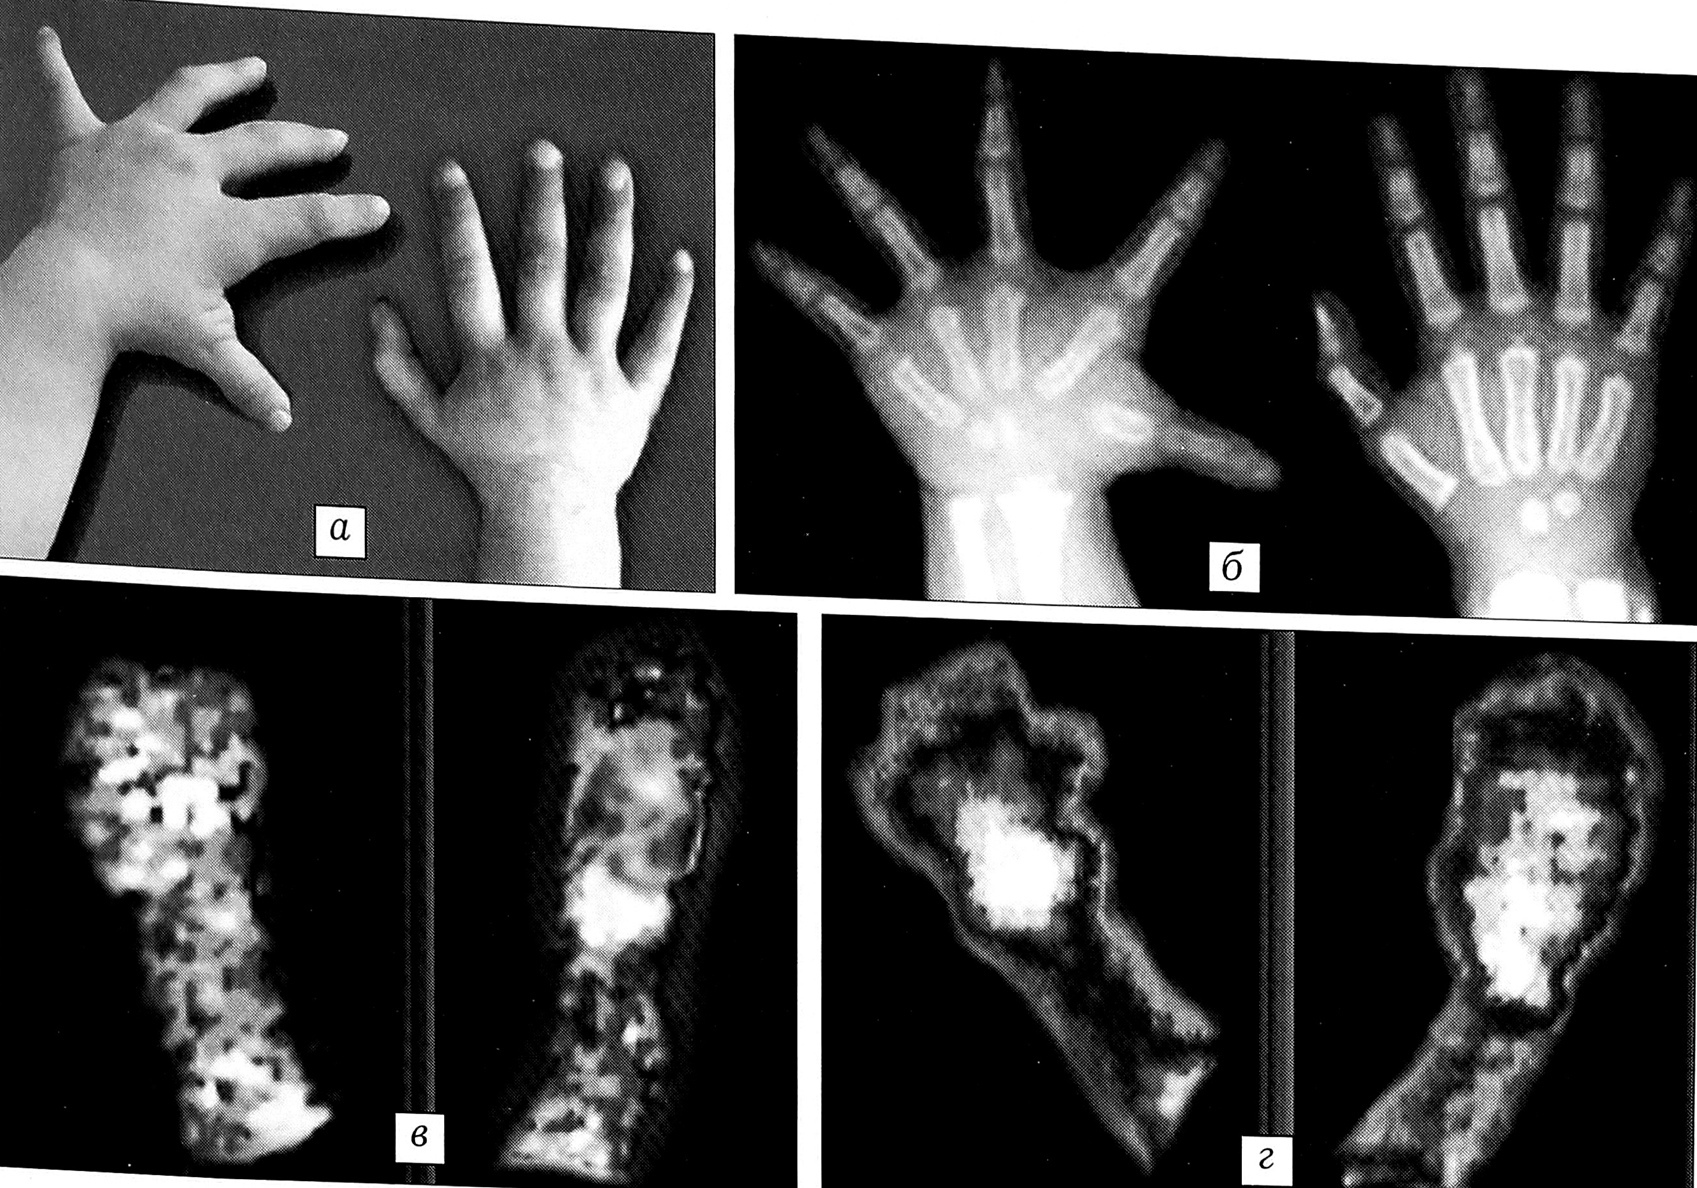

3-я форма. Линейные размеры лучей кисти практически не изменены, увеличены объемные размеры фаланг и костей запястья. Имеется резкая гипертрофия коротких мышц кисти, что приводит к значительному расширению ладони, сгибательным контрактурам и ульнарной девиации в пястно-фаланговых суставах. Значительно нарушена функция схвата (рис. 3).

Рис. 3. Внешний вид (а) и рентгенограмма (б) кистей больной Д. 13 лет с врожденным гигантизмом правой кисти, 3-я форма.

При 2-й форме заболевания (2 больных) в проекции пораженного сегмента констатированы отсутствие локальной гиперемии и равноценный с контролем уровень перфузии. В фазе костной фиксации определялись очаги повышенного накопления РФП (в среднем на 30%) в проекции увеличенных фаланг. Полученные данные указывают на незначительную активизацию процессов костеобразования в пораженном сегменте кисти по сравнению с индивидуальной нормой. В качестве примера приводим данные обследования больной В. с гигантизмом II пальца левой кисти (рис. 5).

Рис. 4. Внешний вид (а) и сцинтиграммы (б, в) кистей больного Б. 2,5 лет с врожденным гигантизмом III пальца левой кисти, 1-я форма. б — фаза перфузии: в проекции III пальца левой кисти определяется диффузное повышение интенсивности кровообращения на 18%; в — фаза костной фиксации: в проекции эпиметафизов фаланг III пальца левой кисти выявляется отчетливая гиперфиксация РФП (дистальный межфаланговый сустав +33%, проксимальный межфаланговый сустав +40%, пястно-фаланговый сустав +33% от нормы).

Рис. 5. Внешний вид (а), рентгенограмма (б) и сцинтиграммы (в, г) кистей больной В. 12 лет с врожденным гигантизмом II пальца левой кисти, 2-я форма. в — фаза перфузии: в проекции II пальца левой кисти признаков гиперемии не отмечается, распределение РФП равномерно и идентично индивидуальной норме; г — фаза костной фиксации: в проекции эпиметафиза дистальной фаланги II пальца левой кисти определяется очаг гиперфиксации РФП (+20%).

Рис. 6. Внешний вид (а), рентгенограмма (б) и сцинтиграммы (в, г) кистей больной К. 2 лет с врожденным гигантизмом левой кисти, 3-я форма. в — фаза перфузии: в проекции левой кисти диффузное повышение интенсивности кровообращения на 40%; г — фаза костной фиксации: в проекции пястных костей левой кисти диффузное повышение накопления РФП (+20%).

У больных с 3-й формой врожденного гигантизма (2 ребенка) определялось умеренное повышение показателей перфузии (на 40%) и костной фиксации РФП (на 20%). Особенностью распределения РФП в костях являлась обширная площадь его фиксации в проекции пястных костей без четкой дифференциации по эпиметафизам и диафизам, что свидетельствовало об активном как периостальном, так и энхондральном остеогенезе. В фалангах выраженных изменений характера и уровня фиксации РФП не выявлено. Иллюстрацией могут служить данные обследования больной К. с гигантизмом левой кисти (рис. 6).